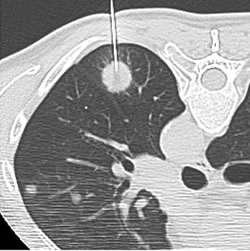

1. Radyofrekans ve mikrodalga Ablasyonu

Girişimsel radyoloji yöntemleri, doktorlara gerçek zamanlı olarak hastanın iç yapısını görmelerini sağlar. Bu, tedaviler sırasında hassas bir şekilde doku örneğinin alınmasını kolaylaştırır ve yanlış yerlere müdahale riskini azaltır.

Girişimsel radyoloji, ameliyatsız tedaviler sırasında iğnenin doğrudan hedef dokuya yönlendirilmesine olanak tanır. Bu, istenmeyen yan etkileri ve hasarı en aza indirir, aynı zamanda daha hassas ve doğru sonuçların elde edilmesine yardımcı olur.